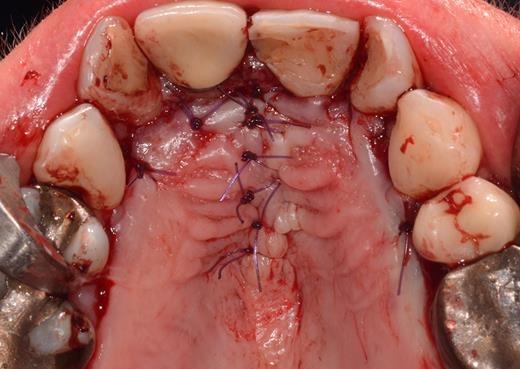

After a sulcular incision on the palatal side from teeth 15 to 25 and an incision in the midline of the palate omitting the incisive papilla and the two orifices of the NPD, two full-thickness mucoperiosteal flaps were raised. Thereafter, the incisive papilla and the whole contents of the incisive canal were enucleated (Figs 4–6). The bony incisive canal was filled with autologous bone harvested from the palatal region (bone scraper) (Fig. 7). A tension-free primary wound closure was achieved by moving the palatal flaps to the midline using single button and interdental vertical mattress sutures (Monocryl 4-0, Ethicon, Johnson & Johnson, USA) (Fig. 8). To avoid wound dehiscence and hematoma, an iodoforme gauze and a palatal plate were applied (Fig. 9). The patient was instructed to rinse three times a day with 0.1% chlorhexidine (formula hospitalis) for 2 weeks postoperatively. Sutures were removed after 14 days.

Situation after removal of the entire soft tissue contents of the incisive canal.